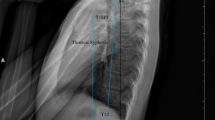

In AIS patients with THK, the overall balance was compensated with an unusual forward leaning posture at pre-operative stage. This was accompanied by a reversed CL, TK and high SS, but normal LL. This posture was corrected with modification during different stages post-operatively, but not to normal values. This indicated that THK patients need to undergo substantial change of their sagittal profiles to find a new improved balance, including a posterior shift of the trunk, whereas a similar maneuver was not necessary for NTK patients. Moreover, this represents a further confirmation immediate post-op postural configuration is mostly transient, and it may not truly reflect long-term surgical results (Fig. 3). Part of these changes in sagittal alignment could be due to behavioral rather than physiological causes, such as increased use of electronics (tablets, smartphones, etc.) in youth18,19.

The schematic diagram on the evolution of changes in the global sagittal profiles of AIS patients with and without thoracic hypokyphosis pre-operative and at different time points post-operative. In AIS patients with thoracic hypokyphosis, the overall balance is compensated with the unusually forward leaning posture (head forward) in pre-operative stage. This posture is corrected with modification during different stages post-operatively. Whereas in AIS patients with normal thoracic kyphosis, the overall balance is maintained with head in a relatively neutral position. There is no significant interval change of the thoracic kyphosis at any time point. The spinal profiles are superimposed on a non-scoliotic spine. The arrow represents the overall balance of the corresponding parameters at each time point: ↗, leaning forward; ↑, medial balanced.